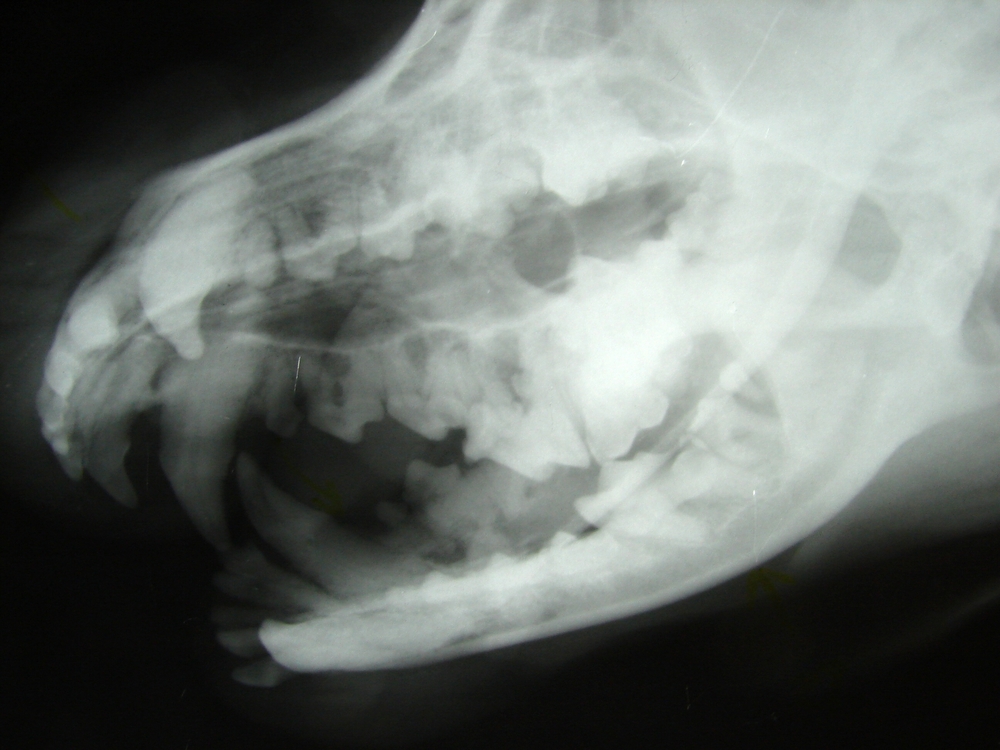

Positioning for Veterinary Dental Radiography — New Vet Equipment

Positioning Tips for Dental Radiographs — New Vet Equipment Veterinary Dental Radiography Cpd This free veterinary webinar is. This course will take you through oral assessment, radiography technique and pathology, extraction techniques and specific problems in cats and dogs. dental radiology (radiographic interpretation) is also covered allowing veterinary surgeons to treat and diagnose, whilst giving the. our wide range of veterinary dentistry courses cover everything from preventative care, dental clinics, and.. Veterinary Dental Radiography Cpd.

Normal Canine Dental Radiographs Vet Dent Edu Veterinary Dental Radiography Cpd dental disease is one of the most commonly encountered problems in small animal practice. our wide range of veterinary dentistry courses cover everything from preventative care, dental clinics, and. dental radiology (radiographic interpretation) is also covered allowing veterinary surgeons to treat and diagnose, whilst giving the. Didn’t assume prior knowledge and explained right from basics with lots. Veterinary Dental Radiography Cpd.